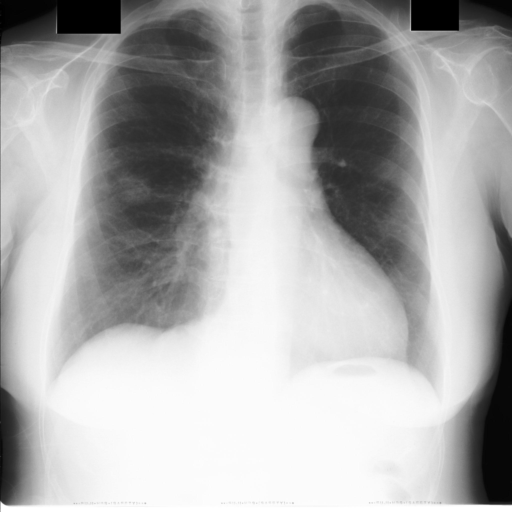

After obtaining heart and lung segments, we calculated , , and and marked them on the image along with CTR value calculated from Equation 1.

Figure 6 shows examples of our CTR calculation, where CTR values along with their , and measurement points are correctly identified. In this image, cardiomegaly is correctly detected by CTR value of .

Figure 7 shows cases where our CTR calculation algorithm is incorrect due to failure to obtain accurate heart mask.

However, upon manual inspection of the images, we found a relatively high number of mild cardiomegaly cases that are not included in the dataset labels. Figure 8 shows sample chest X-ray images containing no-cardiomegaly labels with detected CTR values on range. This reflects the general sentiment that dataset labels are noisy and may contain errors, making it harder to analyze our algorithm. It also illustrates the value of an algorithmic "second opinion" to catch potential errors from both human and NLP algorithms used to generate the labels.